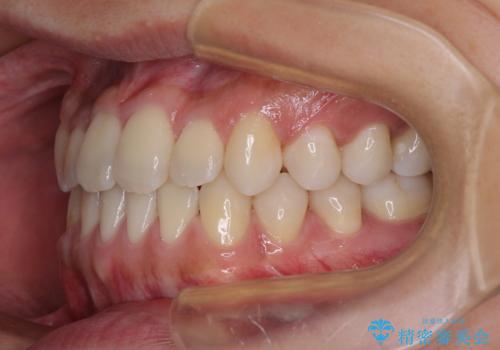

骨格的な左右差も顕著であったため、正中は合わず、上下前歯の一部が接触しない咬み合わせとなることが予想されましたが、正中はもともとのズレが小さかったことから、合わせることができました。

治療期間も10か月間という短期間で終了し、患者様には大変満足していただきました。